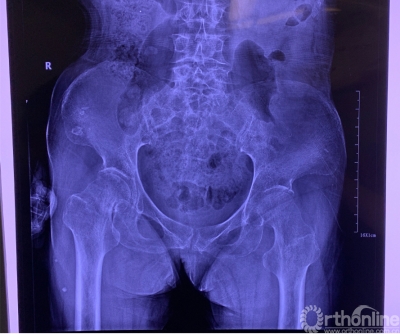

当即将迎来除夕之时,本是顺利过年的73岁贾妈妈,却不小心摔了,到医院一查:右侧股骨颈骨折,同时有肝硬化、血小板低、高龄,加之肝和血的问题,对术者提出了更高的要求。看到老人痛苦祈求的眼神,正准备开启假期模式的北京大学人民医院骨关节科李虎医生只说了一个字:“做!”